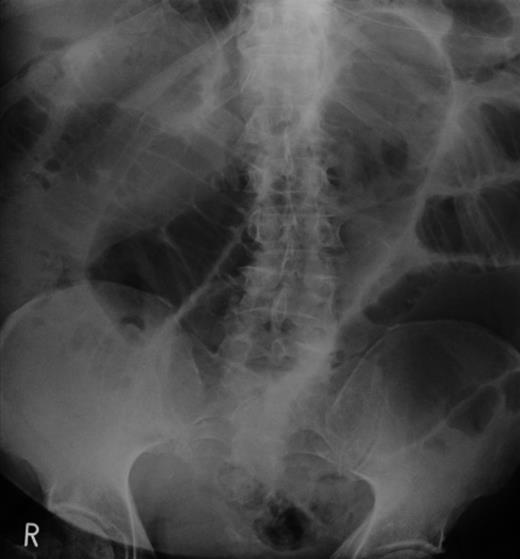

An abdominal X-ray confirmed SBO (Fig. 1). In view of having a virgin abdomen, a CT scan was arranged. This revealed SBO secondary to a mass in the small bowel, causing an ileojejunal intussusception (Fig. 2).